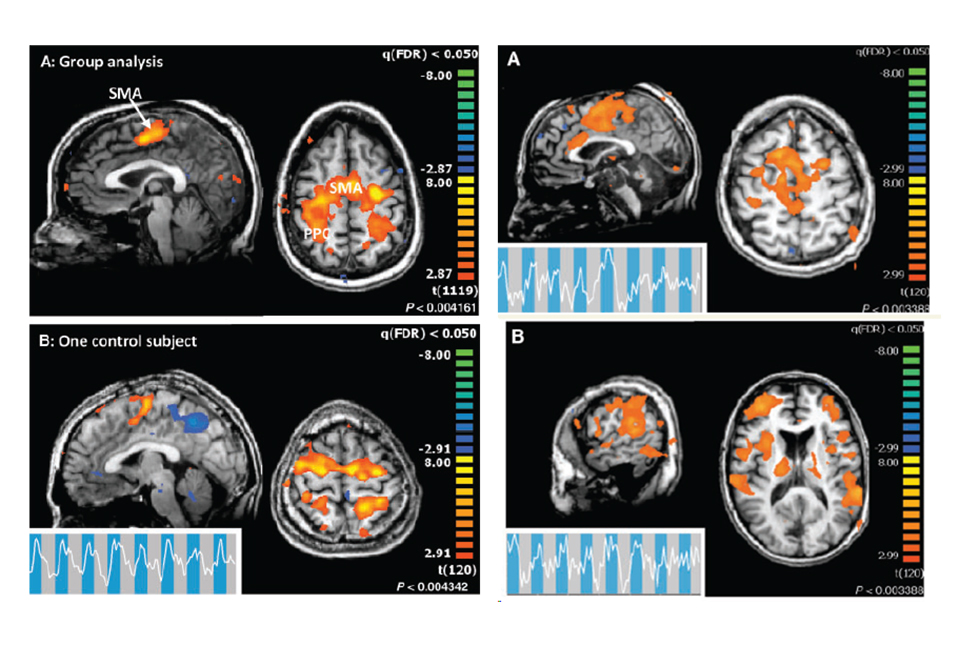

Turns out there are indeed comatose patients who aren't quite comatose. Wow.